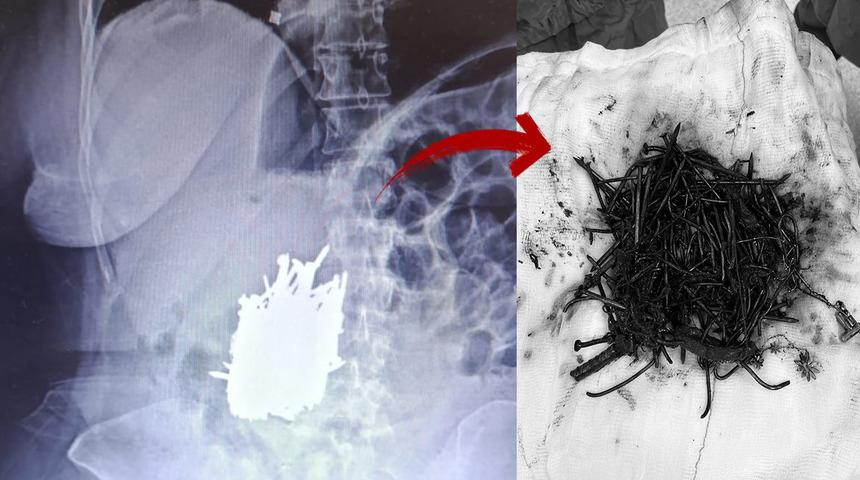

Mersin'in Erdemli ilçesinde karın ağrısı şikayetiyle hastaneye başvuran zihinsel engelli 52 yaşındaki A.K. adlı kadının midesinden çivi, inşaat demiri, kolye, toka gibi çok sayıda metal cisim çıkarıldı.

İlçede yaşayan zihinsel engelli A.K., karın ağrısı şikayetiyle Erdemli Devlet Hastanesi'ne başvurdu. Hastaya yapılan tetkik sonucunda kadının midesinde çok sayıda metal cisim olduğu tespit edildi.

Hasta, genel cerrahi uzmanı Dr. Can Terzier ve ekibi tarafından acilen ameliyata alındı ve midesinden yaklaşık 1 kilo ağırlığında çivi, inşaat demiri, kolye, toka gibi çok sayıda metal cisim çıkarıldı.

Hastanın ameliyatının başarılı geçtiğini, şu anda sağlık durumunun stabil seyrettiğini ve servise alınarak takibinin devam ettiğini belirten Dr. Terzier, zihinsel engeli bulunan hastaların asla yalnız bırakılmaması gerektiğini belirterek, hasta yakınlarının bu konuda duyarlı olmasını istedi.